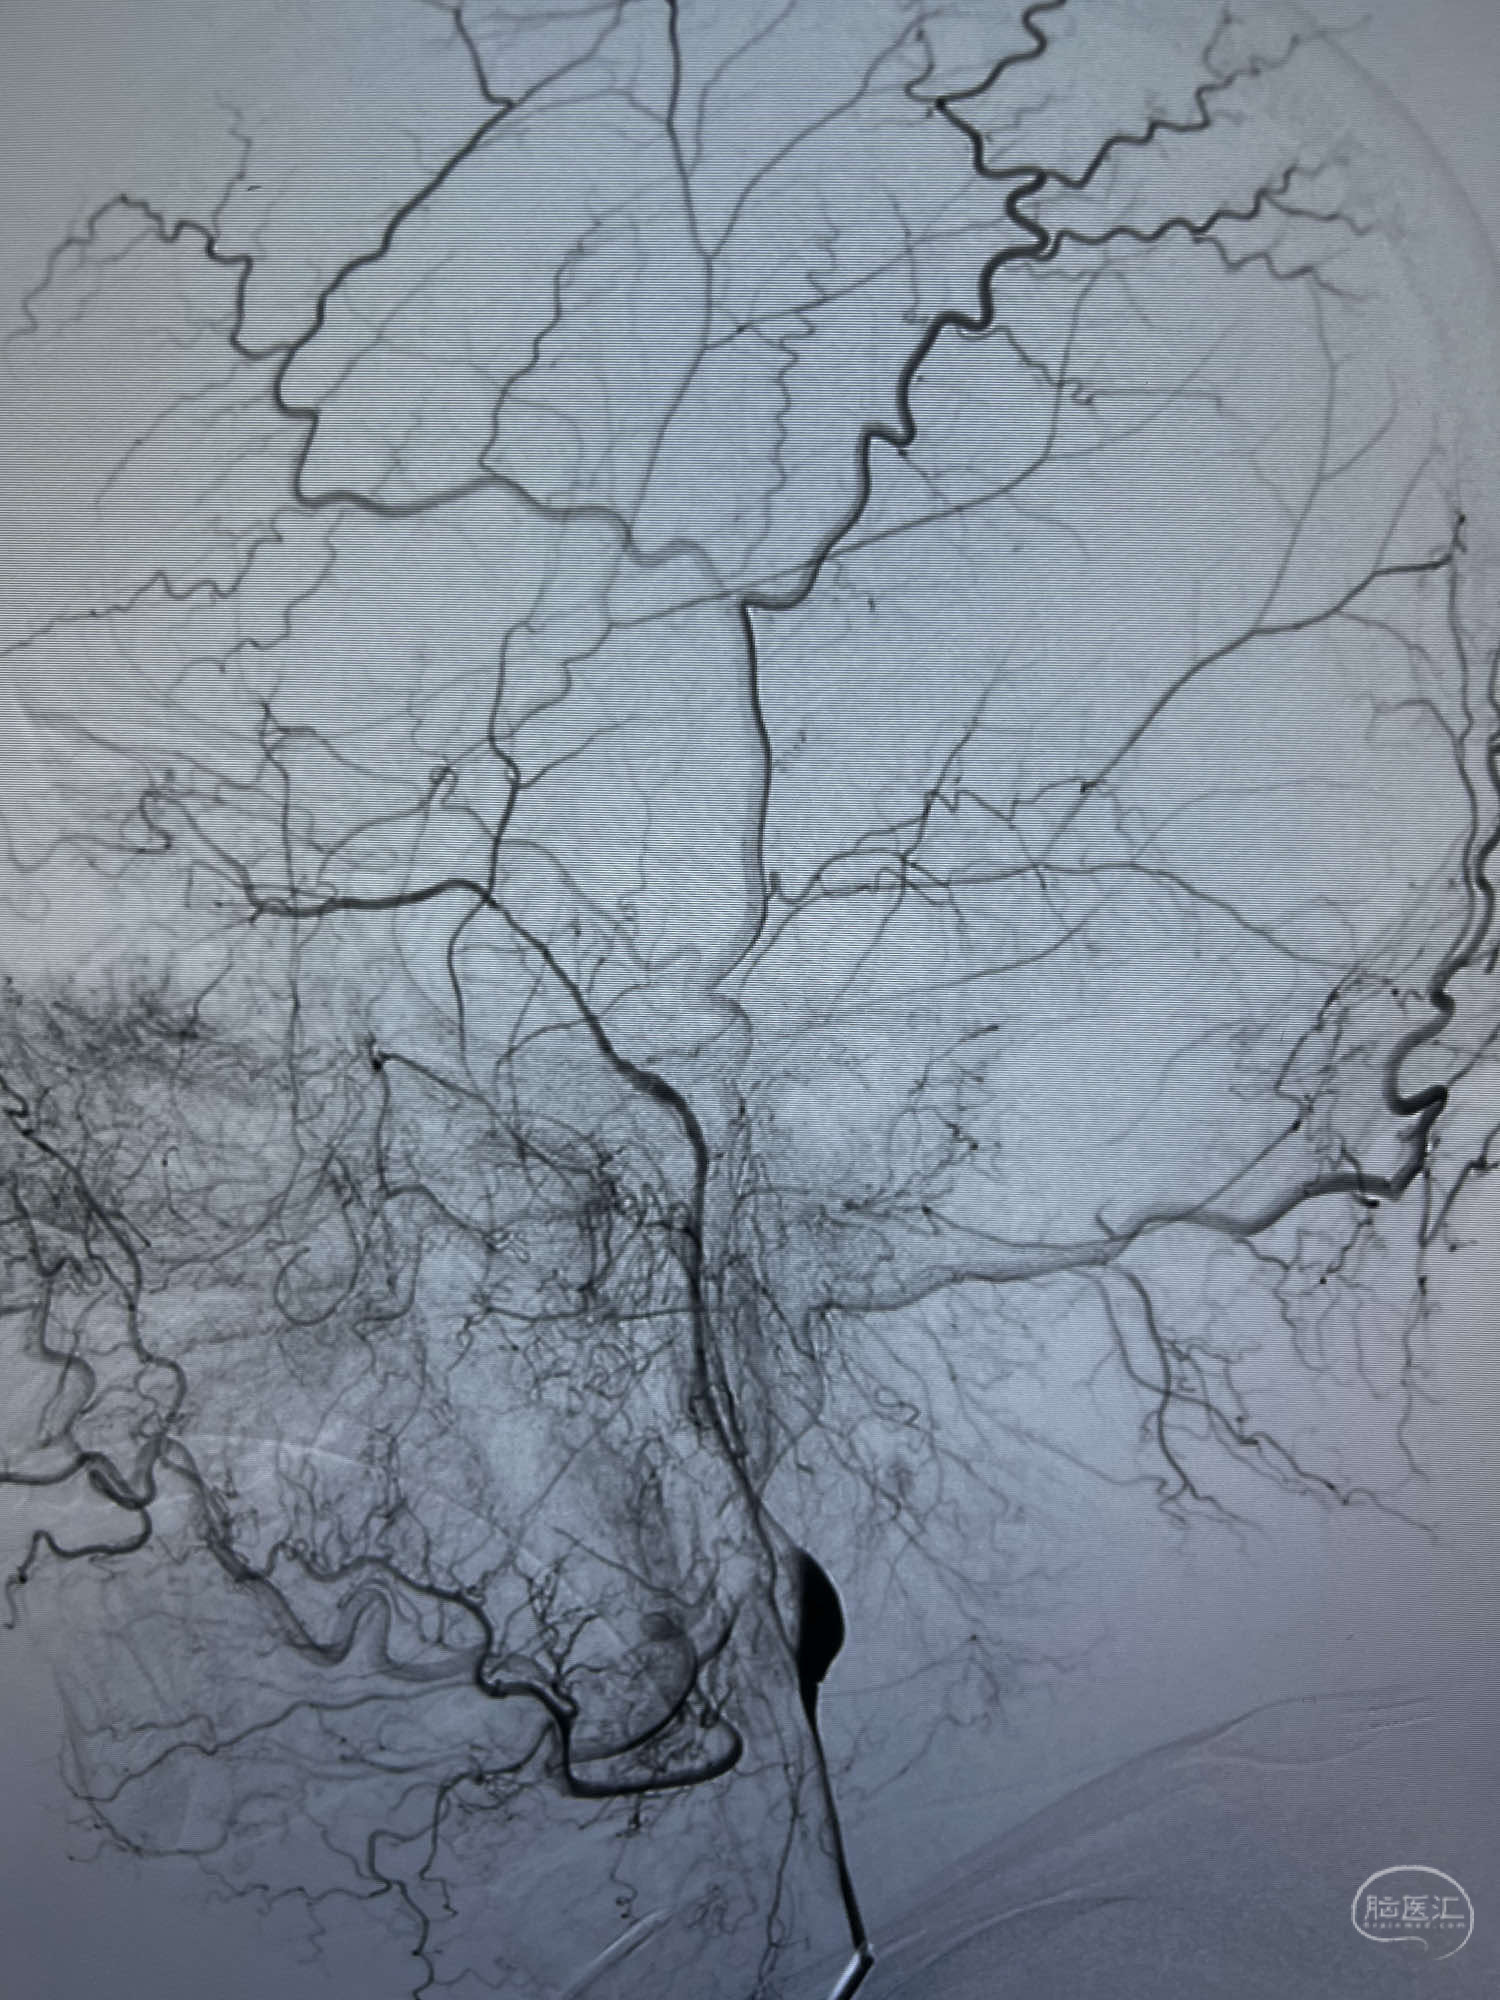

DSA示:左侧颈内动脉眼动脉段以远闭塞,后交通动脉开放,椎基底动脉通过后交通动脉代偿左侧大脑中动脉区域,右侧发出双侧大脑前动脉,右侧大脑中动脉M1末端宽颈动脉瘤,大小约4.3mmx4.6mm。

6F Neuromax➕6F115cm 心玮中间导管建立路径,sychro14微导丝➕VIA21超选至动脉瘤体内近中部,WEB5mmx3mm植入动脉瘤。

WEB瘤内扰流装置5mmx3mm经过“种子、萌芽、开花”三个阶段,打开后良好贴壁,动脉瘤内血液滞留,载瘤动脉通畅。WEB一步到位,通过瘤内扰流的方式起到栓塞动脉瘤的作用,避免了应用支架保护分支血管,简化了操作步骤,降低了术中血栓及出血的风险。